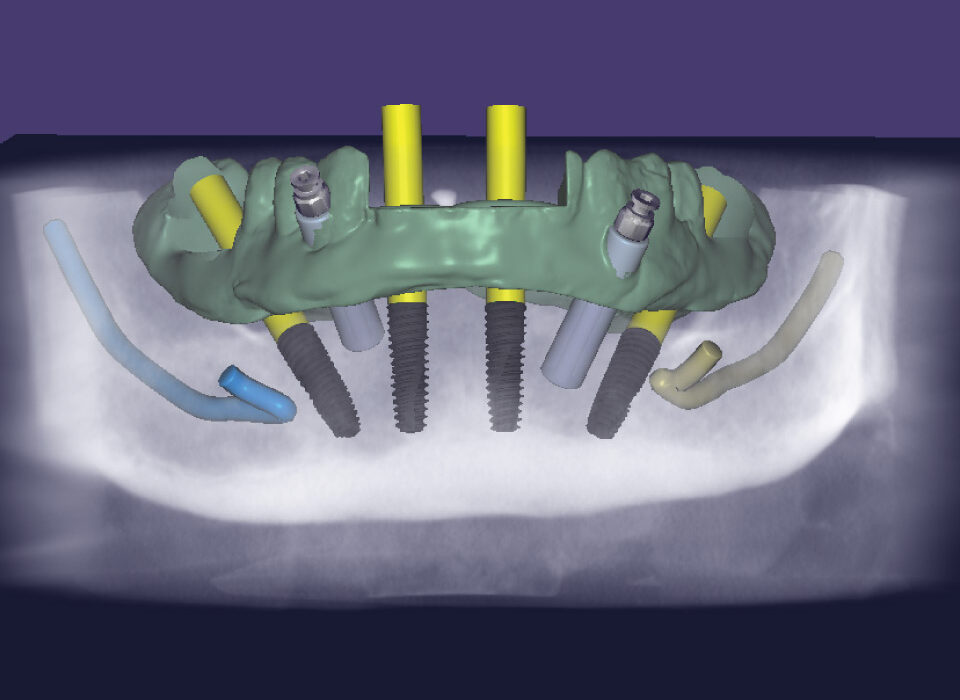

Surgical Guides

Surgical Guide is a digital tool that ensures accurate positioning and angulation of implants, which is crucial for the success and longevity of the implant. We fabricate different types of surgical guides, including tooth-borne, mucosa-borne, and bone-borne guides i.e stackable.